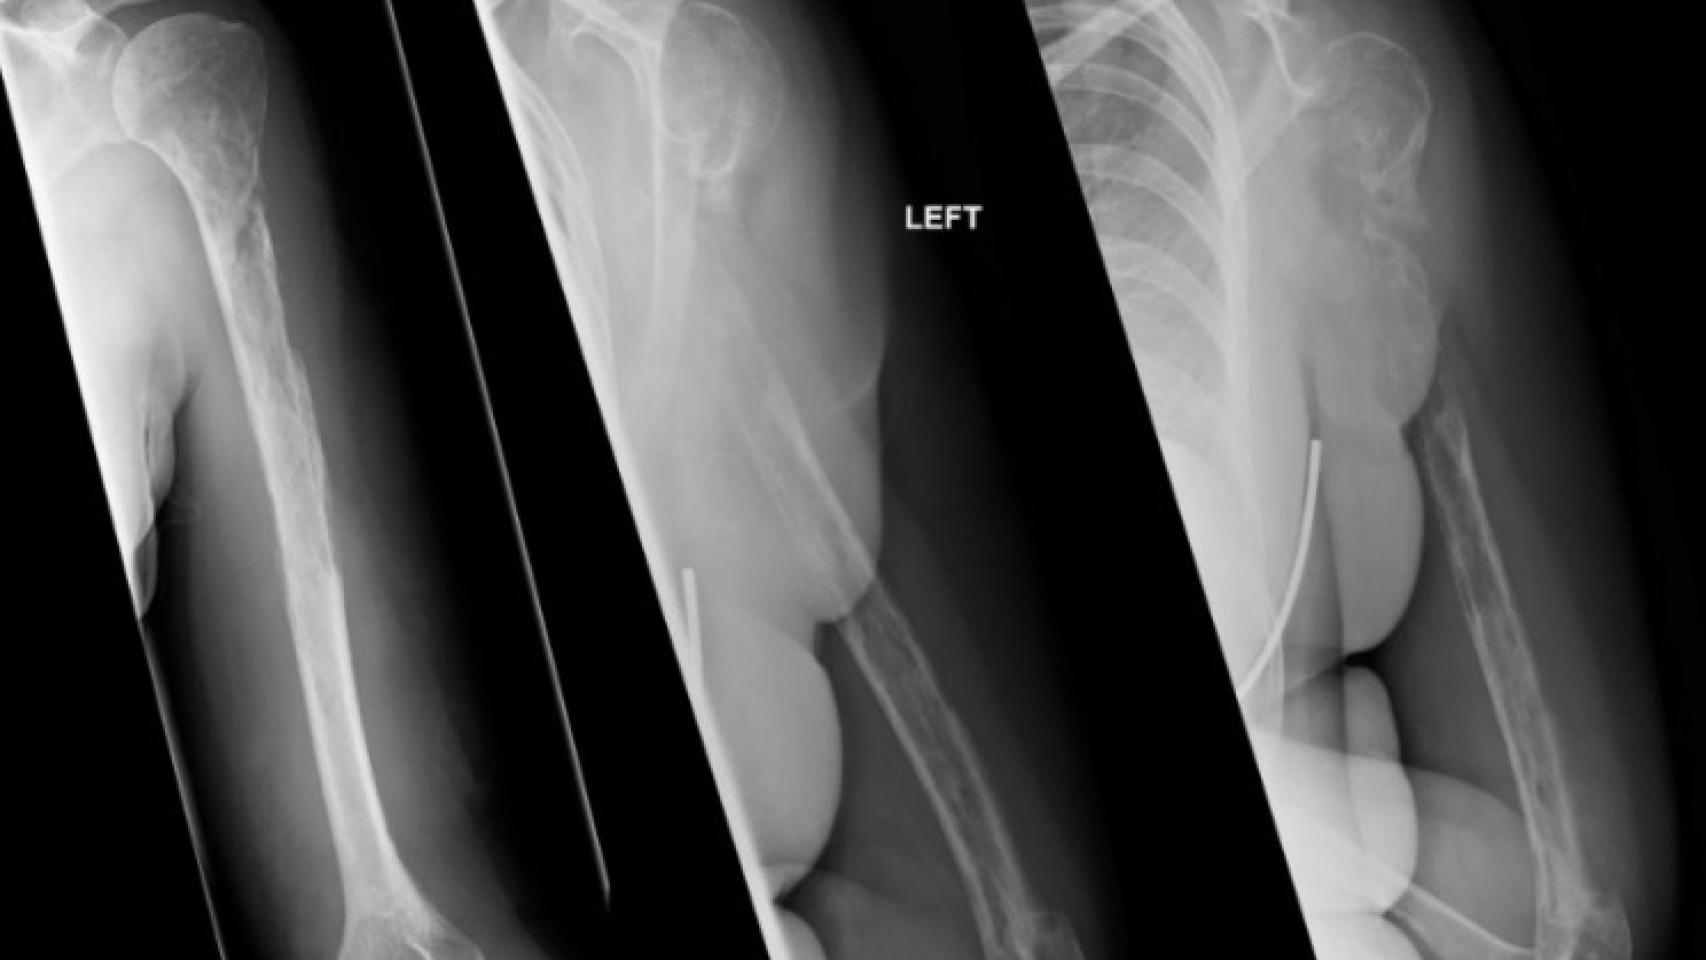

Las primeras pruebas parecían apuntar a un tumor, pero la biopsia descartaba esta posibilidad, por lo que el origen de su padecimiento parecía todo un misterio. Fueron necesarios 18 meses y varias fracturas óseas para que una nueva radiografía desvelara la peculiar realidad: sus huesos estaban desapareciendo.

La paciente sufría la enfermedad de Gorham-Stout, o síndrome del hueso fantasma, una rara patología que se caracteriza por un deterioro progresivo de los huesos, paralelo a la proliferación y dilatación de los vasos linfáticos.

Aunque puede darse en cualquier pieza ósea, el hueso que más a menudo se ve afectado por esta enfermedad es el húmero -en ocho de los 64 casos-, como en el caso de la paciente escocesa, que han relatado sus médicos en la revista BMJ Case Reports.